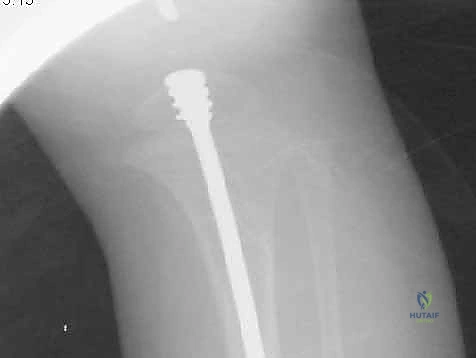

الدليل التفصيلي لخطوات العملية الجراحية: بضع العظم عبر الجلد والمسامير التلسكوبية

تُعد هذه العملية من أدق العمليات في جراحة عظام الأطفال، وتتطلب مهارة استثنائية كما هو الحال مع البروفيسور محمد هطيف. يتكون المسمار التلسكوبي (Fassier-Duval) من جزأين يتداخلان ببعضهما البعض (مثل التلسكوب). يتم تثبيت أحد الأطراف في أعلى العظم والطرف الآخر في أسفله. عندما ينمو العظم، ينزلق الجزء الداخلي من المسمار للخارج، مما يسمح للعظم بالنمو الطبيعي دون أن ينثني أو ينكسر.

الخطوة الثالثة: بضع العظم المتعدد عبر الجلد (Multiple Percutaneous Osteotomies)

بدلاً من فتح الساق بالكامل، يقوم الدكتور هطيف بعمل ثقوب صغيرة جداً (مليمترات) في الجلد. باستخدام أدوات دقيقة جداً (مثل الإزميل الدقيق أو المثقاب المتخصص)، يتم قطع العظم في أماكن التقوس من الداخل دون إتلاف الأنسجة الرخوة أو العضلات المحيطة. هذا يحافظ على التروية الدموية للعظم (Periosteum)، مما يسرع من التئام العظم بشكل مذهل.

الخطوة الرابعة: إدخال المسمار التلسكوبي

بعد تقويم العظم وجعله مستقيماً كحبات المسبحة على خيط، يتم إدخال السلك الدليلي (Guide Wire). ثم يتم إدخال الجزء الخارجي (الأنثوي) من المسمار التلسكوبي وتثبيته في الجزء العلوي من العظم (Epiphysis).

بعد ذلك، يتم إدخال الجزء الداخلي (الذكري) من المسمار عبر الجزء السفلي من العظم وتثبيته في المشاشة السفلية. هذا التصميم العبقري يضمن حماية العظم بالكامل من الداخل.

- يتم إجراء أشعة سينية للتأكد من بدء تكوّن الدشبذ العظمي (Callus) حول مناطق القص.